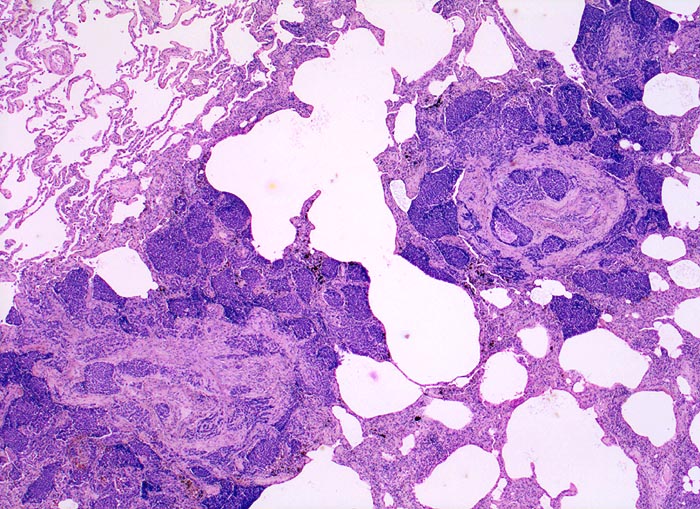

PathoPic – image database / PathoPic ID 4730 - Lymphangiosis carcinomatosa

Lymphangiosis carcinomatosa

Lunge

Dunkle solide Tumorinfiltrate füllen erweiterte Lymphgefässlichtungen um einen zentralen Pulmonalarterienast. Der Tumor greift auch auf das angrenzende Parenchym über.

Metastasierendes Tumorleiden bei unbekanntem Primärtumor. Autoptisch primäres peripheres neuroendokrines Karzinom der Lunge mit ausgedehnter lymphogener und hämatogener Metastasierung.

Histologie

25